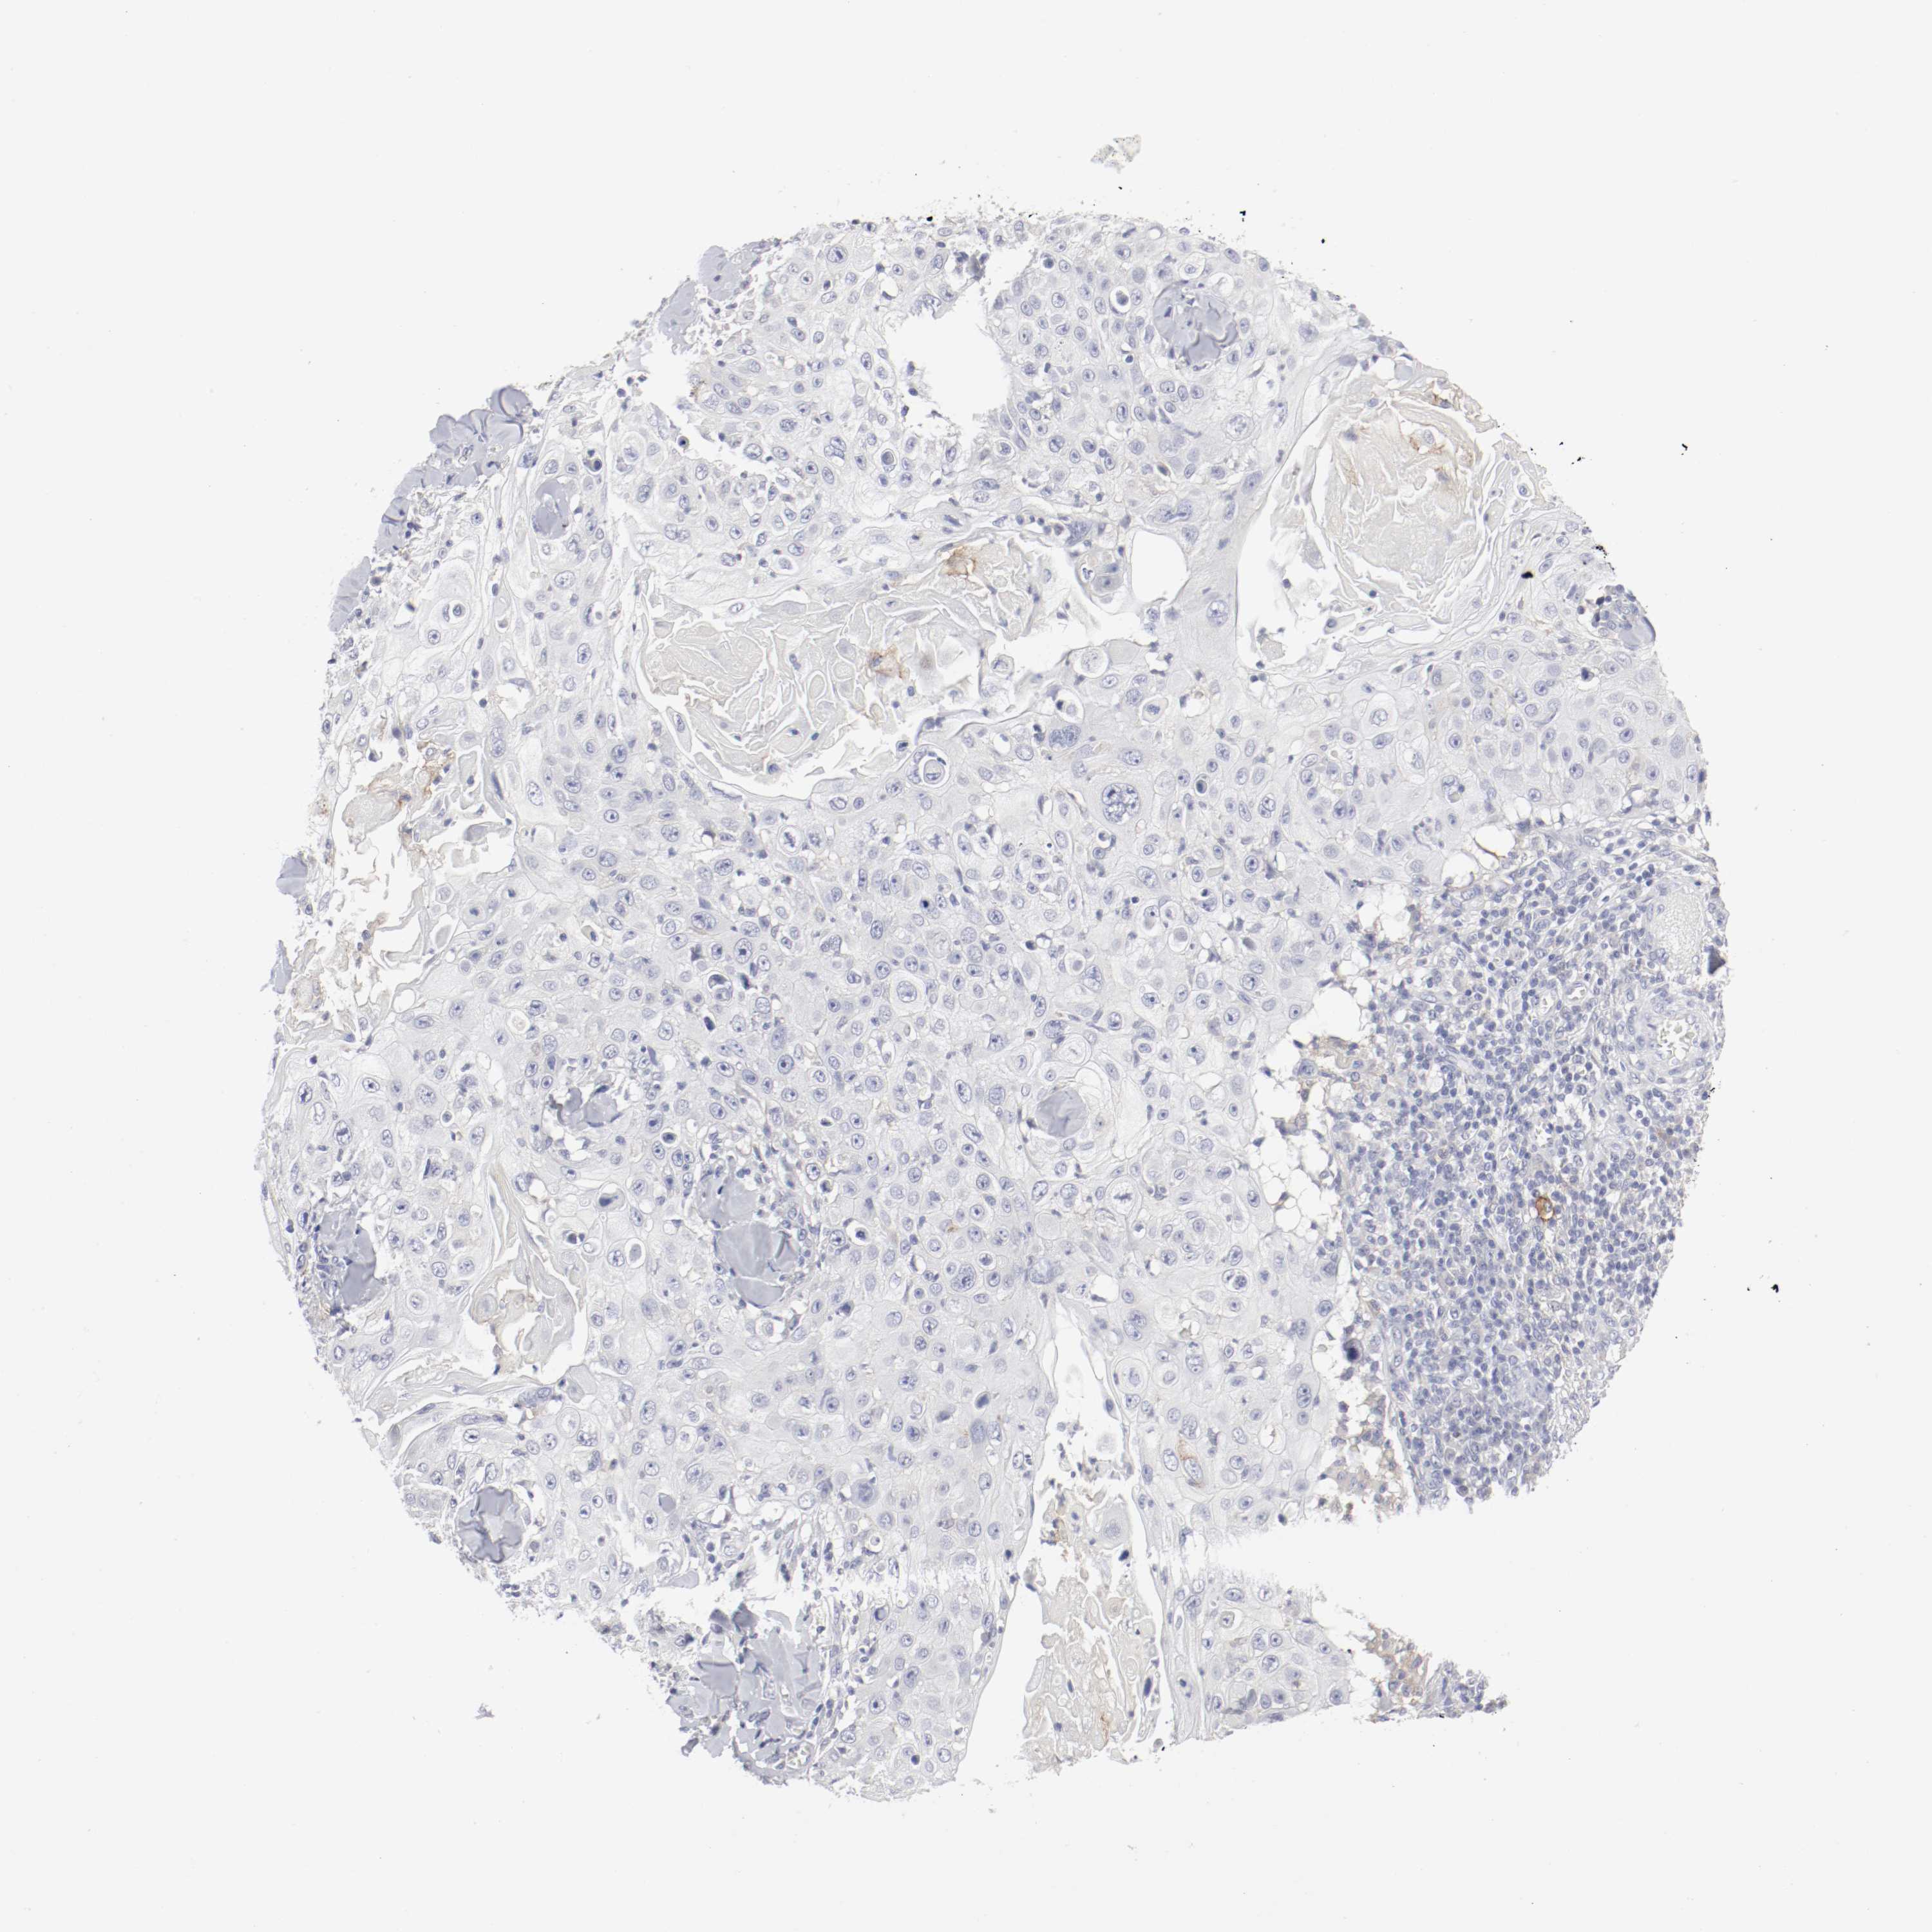

SKIN CANCER - Protein expressioni

A mouse-over function shows sample information and annotation data. Click on an image to view it in a full screen mode. Samples can be filtered based on level of antibody staining by selecting one or several of the following categories: high, medium, low and not detected. The assay and annotation is described here.

Antibody stainingi

Antibody staining in the annotated cell types in the current human tissue is reported as not detected, low, medium, or high, based on conventional immunohistochemistry profiling in selected tissues. This score is based on the combination of the staining intensity and fraction of stained cells.

Each image is clickable and will lead to virtual microscopy that enables deeper exploration of all samples and also displays staining intensity scores, fraction scores and subcellular localization as well as patient and tissue information for each sample.

Antibody HPA004723

Antibody CAB004458

Squamous cell carcinoma, NOS

Basal cell carcinoma